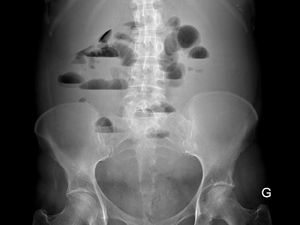

As bridas intestinais são suspeitadas num doente que refira dor/distensão abdominal frequentes e que tenha tido alguma cirurgia abdominal...

Sintomas e complicações das bridas intestinais?

O que são bridas intestinais?

As bridas intestinais (também conhecidas como aderências) são estruturas fibrosas de tecido cicatricial e que unem (colam) os diferentes...